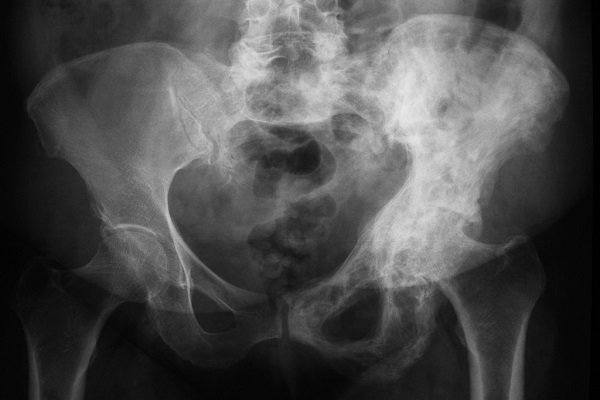

- X-quang: để xác định mức độ bệnh và vị trí của các vùng xương bị ảnh hưởng.

- Biến dạng xương: Bệnh Paget xương có thể gây ra biến dạng xương, làm cho xương trở nên cong hoặc dễ gãy hơn. Biến dạng xương cũng có thể gây ra các triệu chứng khác như khó thở và đau lưng.

- Kích thước xương tăng: Bệnh Paget xương có thể làm cho xương trở nên dày hơn và kích thước tăng lên. Điều này có thể gây ra các triệu chứng như khó thở và đau lưng.